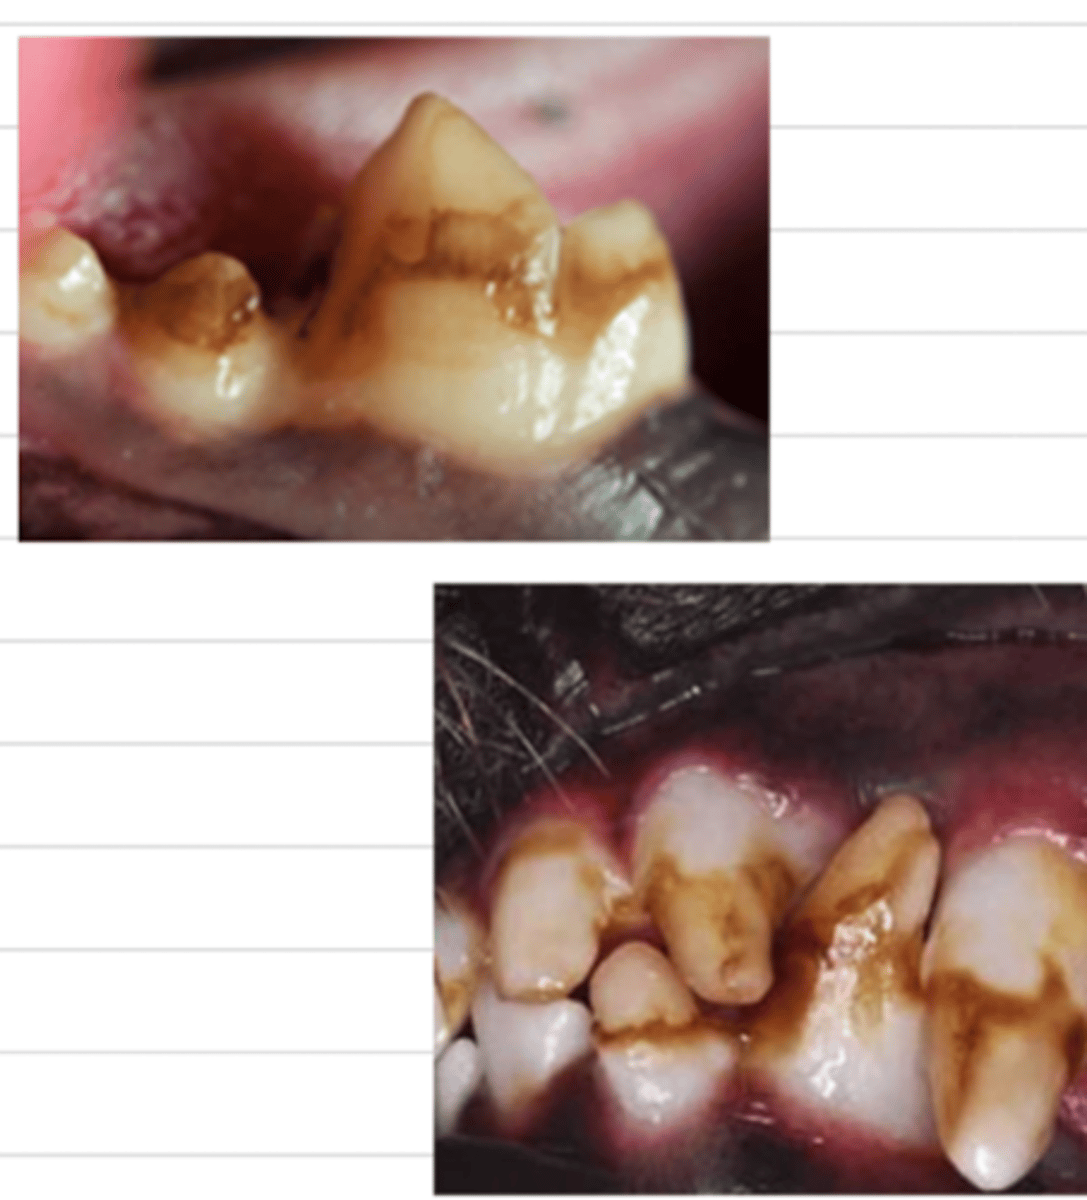

gingivitis (due to tartar)

what problem does this dog have?

gingivitis; viral infection

what is the medical term for the condition of this cat? what is likely the etiology?